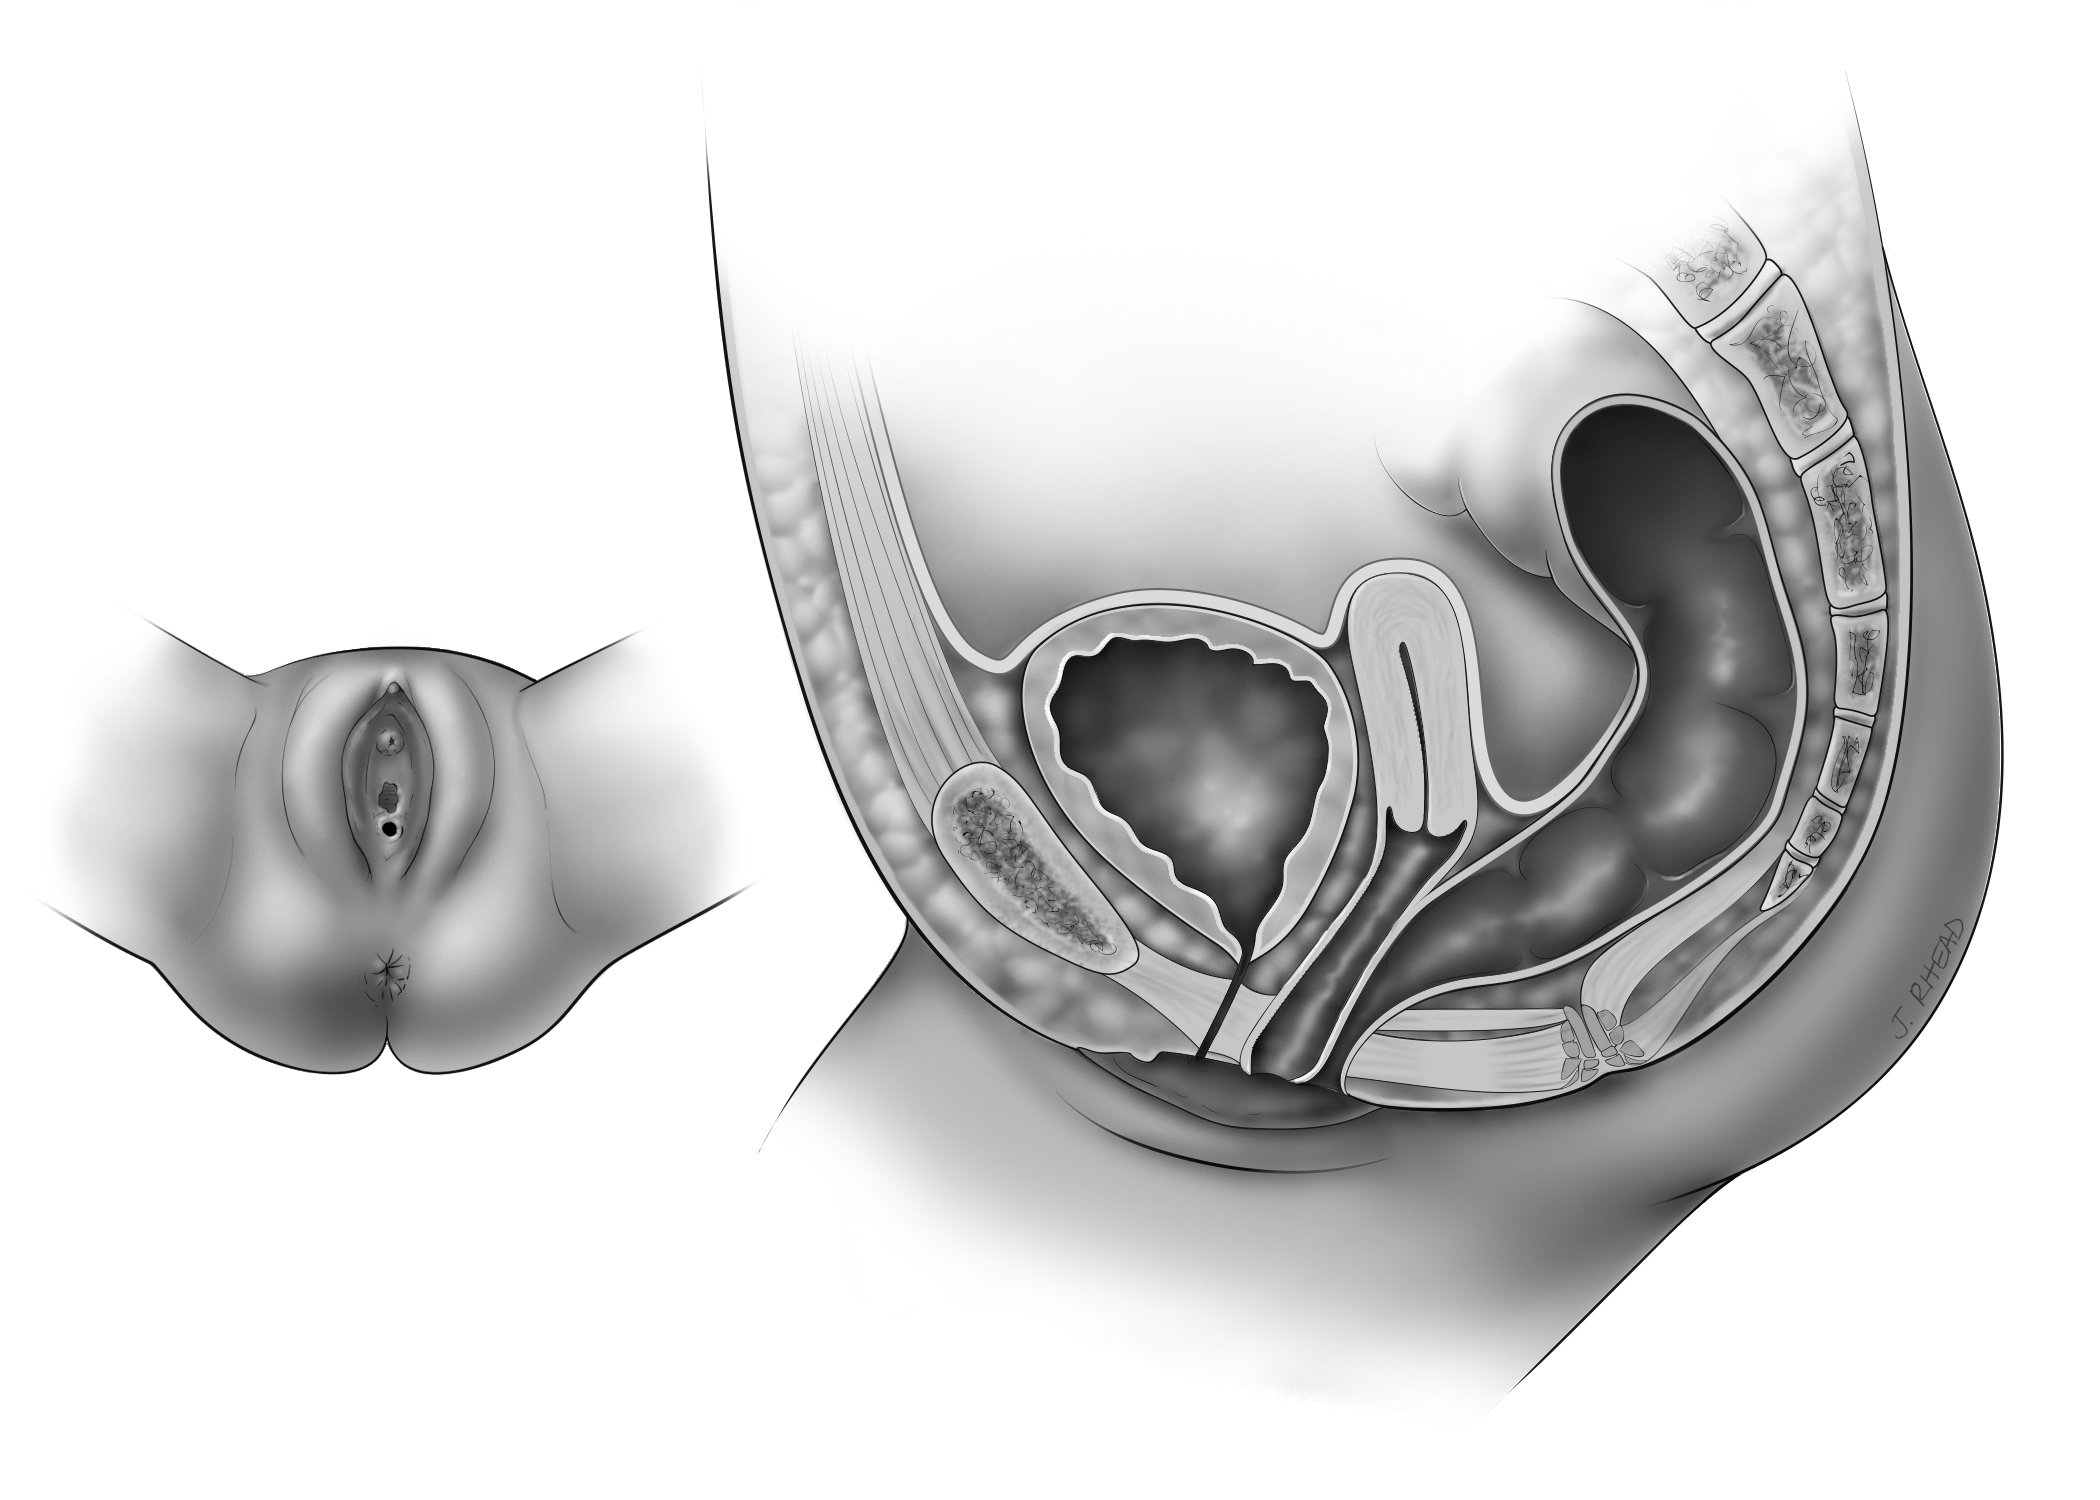

Anorectal malformations involve a wide spectrum of defects. Imperforate anus is when there is no opening at the end of the digestive tract, where the anus is normally located. The rectum (the end of the colon) may end in a closed pouch in the body, or it may connect to the genitourinary tract; this is called a fistula. Sometimes the anus is small and in an abnormal position on the bottom, which prevents natural passage of stool; this is called an anterior anus or perineal fistula. A persistent cloaca is a complex malformation in which the rectum, vagina, and urinary tract meet in a common channel. In children born with cloaca, only one opening will be visible in the perineum compared to the normal anatomy which has 3 separate openings.

Cloaca

The rectum, urethra, and vagina fuse into a common channel, with one opening in the perineum

Perineal Fistula

The anus is located in front of where the anus is normally placed or is too small

Imperforate Anus Without Fistula

The rectum ends in a blind pouch with no opening on the bottom

Rectobulbar Fistula

The rectum connects to the urethra in a male; there is no opening on the bottom

Vestibular Fistula

The rectum opens just behind the vagina (the space between the vaginal hymen and perineal skin).